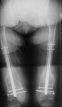

KEMMD> method of treatment for distal femur fractures

A new toy is more interesting and fashionable. And anyway it is not panacea, i have already seen presentations with LISS failures like the attached one presented by D.Seligson. And people also demonstrated incisions say that the method is not so LESS invasive as it supposed to be.